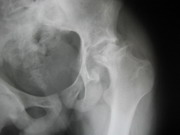

Besides routine trauma, we specialize in advanced traumatology. We manage all the pelvic and acetabular fractures and spinal fractures with neurological deficit, with equal case.